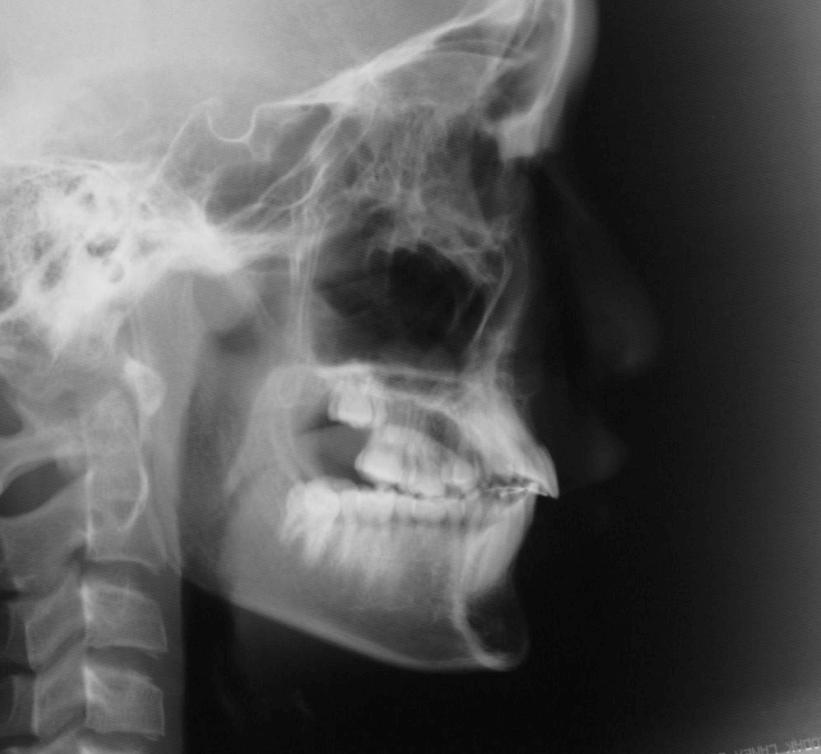

上歯前突+叢生症例 成長期

主訴 | 口元の突出感と歯並びが気になり、将来的な咬合状態を整える目的で来院された患者様です。 |

---|---|

診断結果 | 11歳1か月の女性。骨格的には日本人標準に近く、歯性の上顎前突および叢生が認められました。上下顎ともに歯列のスペース不足があり、永久歯の萌出や歯列の整列に支障をきたす可能性があると診断されました。 |

治療内容 |

|

治療後の経過 | 動的治療終了後は、上下顎の歯列が整い、口元の突出感と叢生が改善されました。審美的・機能的なバランスが取れた状態となり、現在は取り外し式リテーナーを使用し、保定期間に移行しています。 |

治療期間 | 動的治療期間:2年6か月 通院回数:25回 |

治療費用 | 720,000円 |